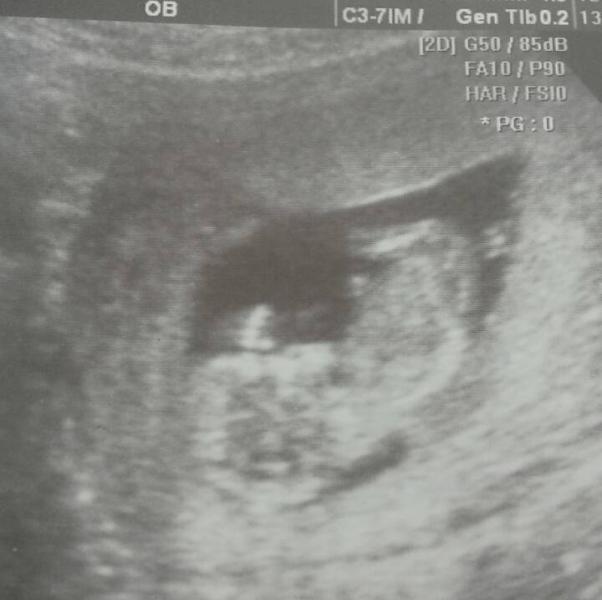

наш первый скрининг...малыш хорошо набирает вес, а вот я сама на оборот теряю вес...с 7 недели минус 2 кг, гинеколог ругает.... (((